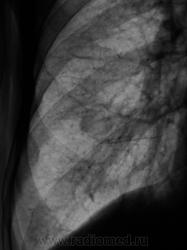

Валентин Львович, может всего навсего сосок...ведь и с противоположной стороны есть нечто подобное, но менее интенсивное и четкое, а то не поверю, что Вами не сделана томограмма для уточнения сего состояния.... ....а треугольный инфильтрат, видимый в бокой проекции, как мне кажется, не соответствует округлой тени проекционно...или я не прав?

....а треугольный инфильтрат, видимый в бокой проекции, как мне кажется, не соответствует округлой тени проекционно...или я не прав?

Уточнение локализации - тень слабоинтенсивная, на бок. снимке не видно. Учитывая, что ребра поломаны были, это может быть просто плевральным наслоением.